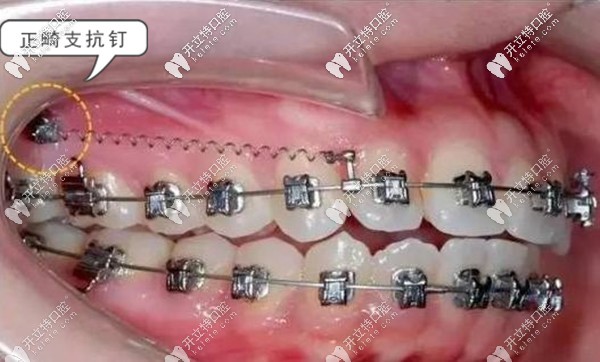

支抗釘——俗稱骨釘,支抗釘主要是拉間隙調(diào)整牙位,也就是借力用的。支抗骨釘不但可以解決牙齒的深覆合咬合問題,也可以讓矯正過程中的牙齒移動更快,還可以改善露齦笑、齙牙等問題。

牙齒矯正支抗釘?shù)淖饔? border=